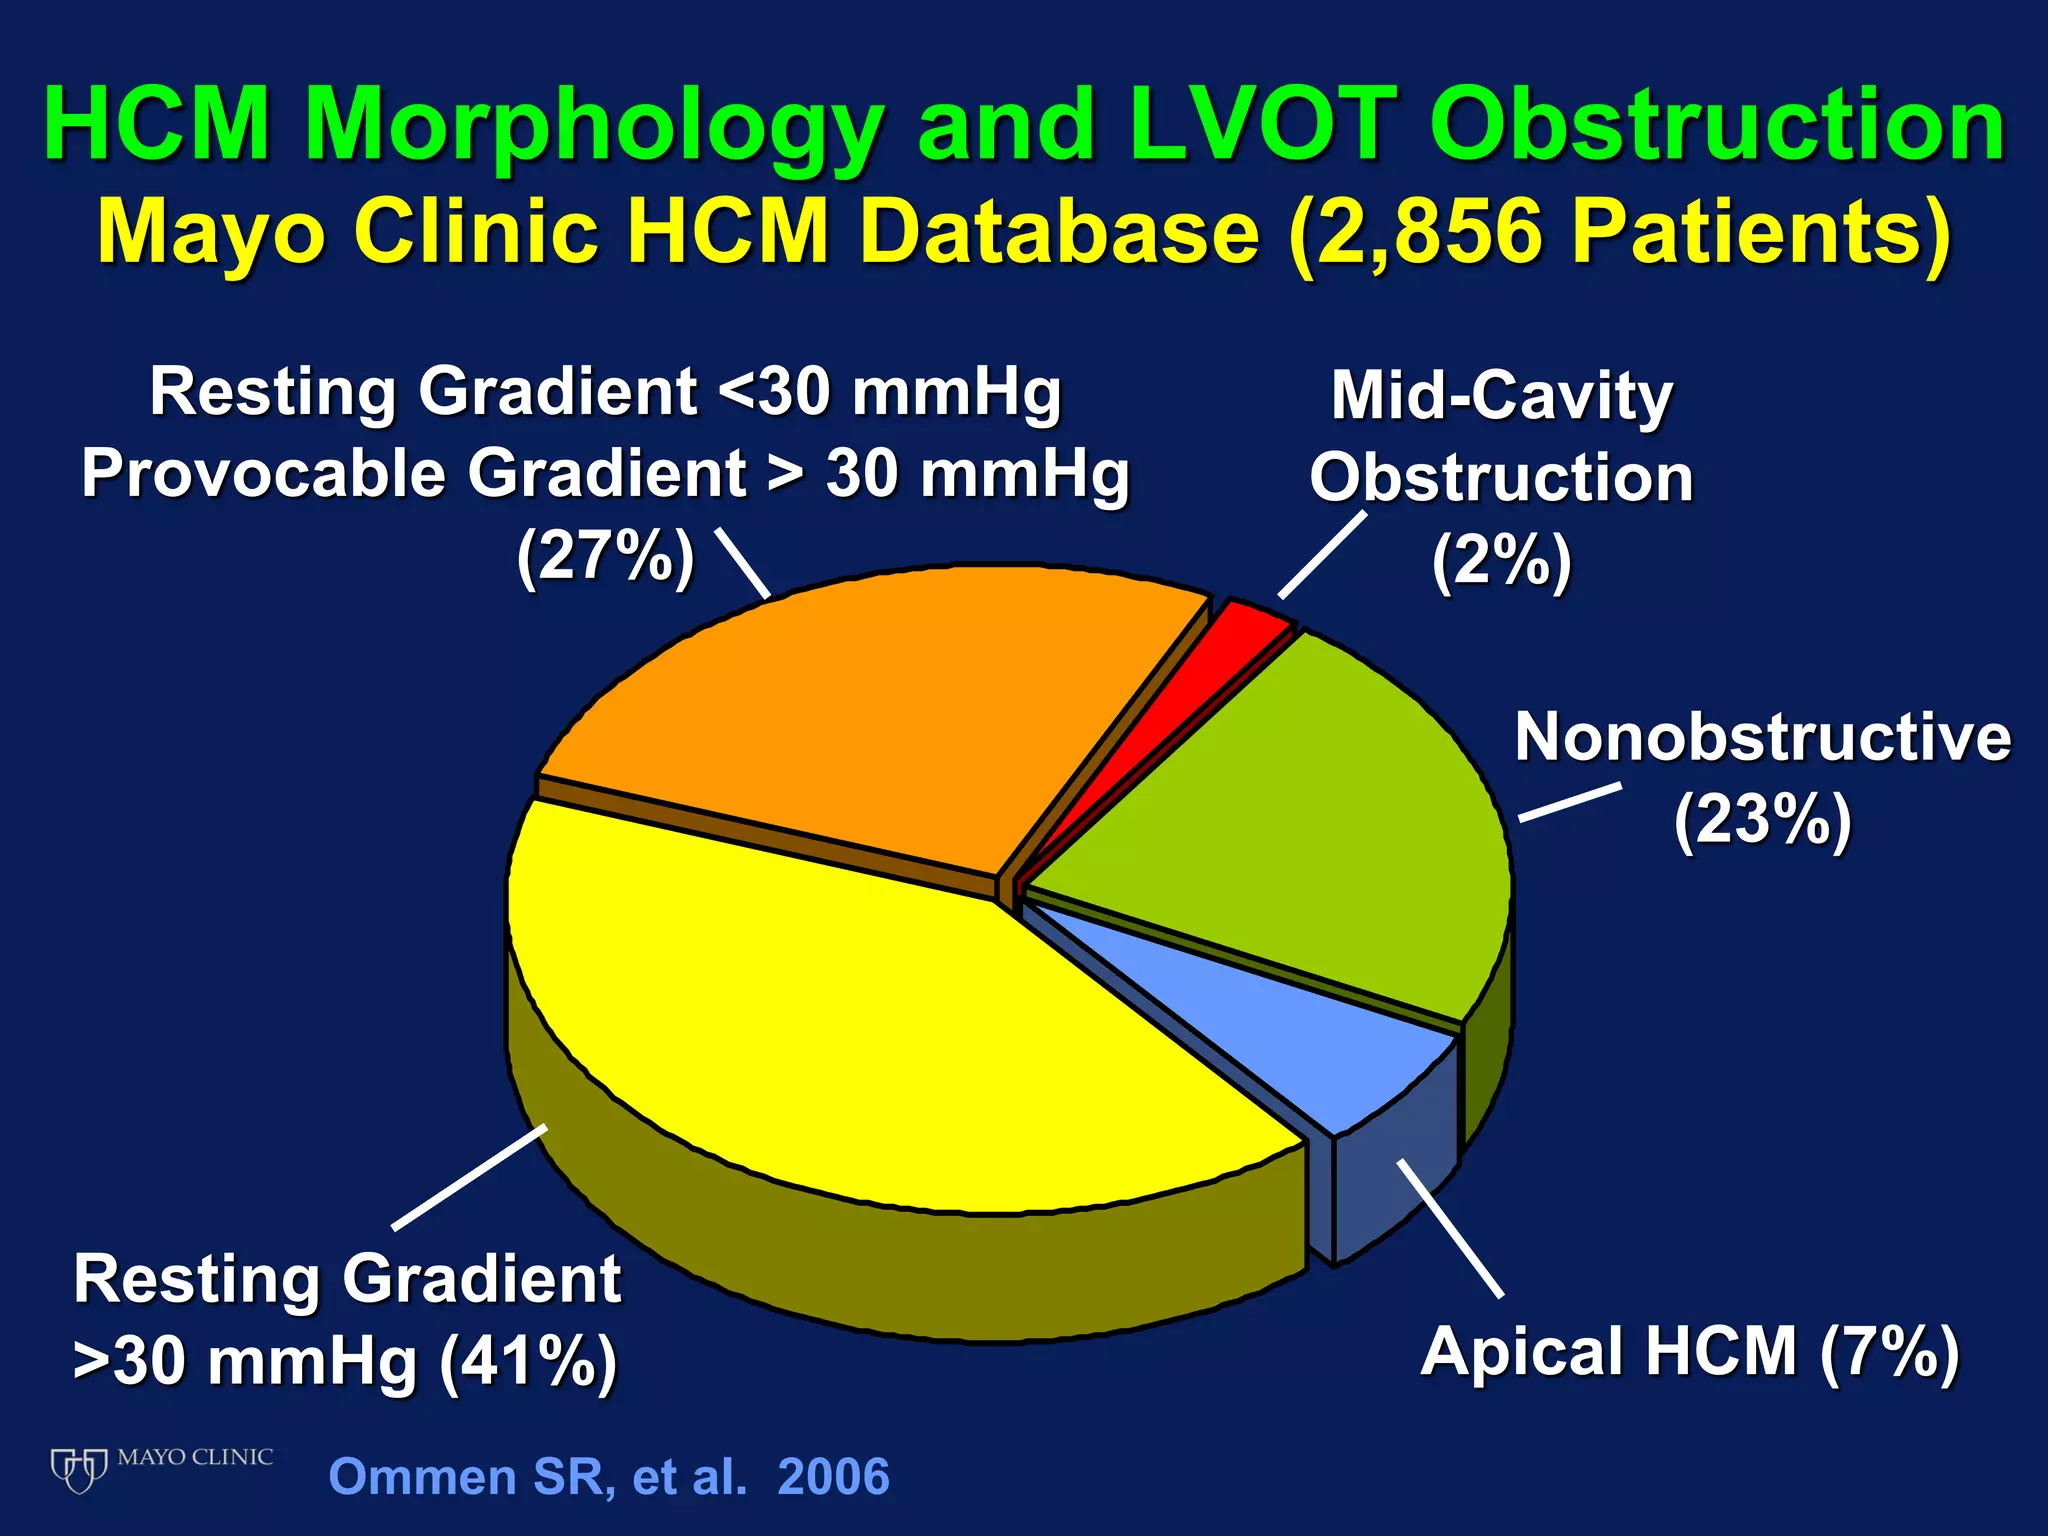

Echocardiography plays an essential role in diagnosing hypertrophic cardiomyopathy (HCM) by demonstrating left ventricular hypertrophy of 15mm or greater that is asymmetric and cannot be attributed to another cause. Echocardiography can also identify the characteristic patterns of hypertrophy such as sigmoid septum, reverse curvature of the septum, and apical hypertrophy. It is used to detect complications of HCM such as left ventricular outflow tract obstruction, mitral regurgitation, and apical aneurysms. Risk stratification for sudden cardiac death utilizes echocardiography to identify features such as massive hypertrophy, abnormal blood pressure response to exercise, and nonsustained ventricular tachycard